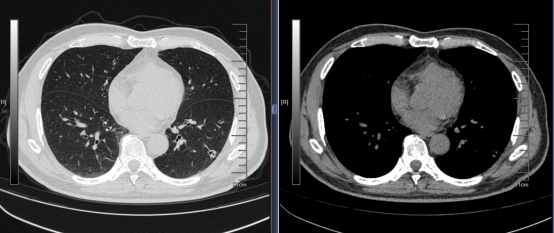

4月1日,62歲的蘇先生因冠心病在泰康同濟(武漢)醫(yī)院心內(nèi)科就診時,胸部CT檢查意外發(fā)現(xiàn)其左下肺有一處13mm的混合磨玻璃結(jié)節(jié),結(jié)節(jié)內(nèi)存在空泡征且邊緣模糊。面對疑似惡性腫瘤的檢查結(jié)果,蘇先生一度陷入焦慮,家人希望早點手術(shù)解決問題。

為明確診斷,泰康同濟(武漢)醫(yī)院心內(nèi)科迅速啟動肺結(jié)節(jié)多學(xué)科聯(lián)合診療(MDT)機制。腫瘤科主任戈偉團(tuán)隊結(jié)合影像學(xué)特征分析指出,該結(jié)節(jié)雖存在一定惡性征象,但也不能排除感染性病變的可能性。經(jīng)團(tuán)隊討論,最終為蘇先生制定了“先進(jìn)行CT引導(dǎo)下經(jīng)皮肺穿刺活檢,明確病理診斷后再決定后續(xù)治療”的診療方案。

由于結(jié)節(jié)體積小、內(nèi)部存在空泡,穿刺難度較大,戈偉主任團(tuán)隊憑借豐富的臨床經(jīng)驗與精準(zhǔn)操作,成功完成活檢。病理結(jié)果顯示為肺隱球菌病,屬感染性疾病,無需手術(shù)切除。這一精準(zhǔn)診斷不僅消除了患者的恐慌,更避免了不必要的手術(shù)風(fēng)險。